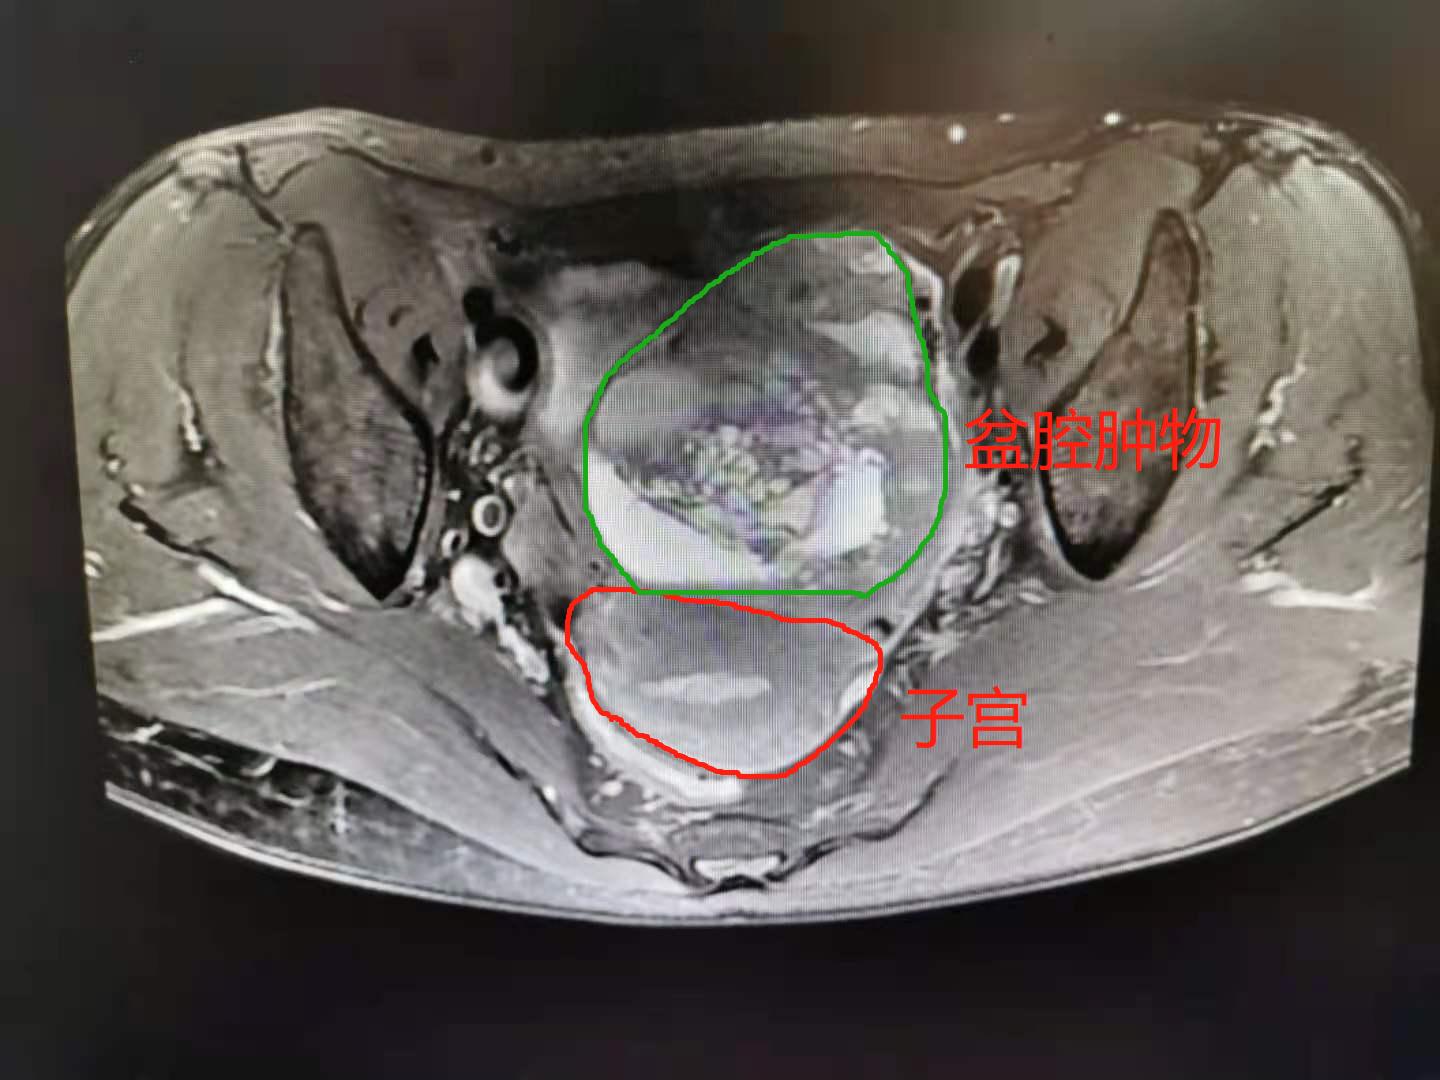

52岁的曹女士因“发现盆腔包块半月”入院,影像学提示卵巢囊腺瘤可能。入院后完善相关检查,医生诊断盆腔包块,性质待查,怀疑卵巢肿瘤。经过陈琦教授团队及科室成员讨论后,5月30日行单孔腹腔镜探查,术中冰冻提示左侧卵巢性索间质肿瘤(低度恶性),按妇科恶性肿瘤诊治指南,需行卵巢恶性肿瘤全面分期手术。